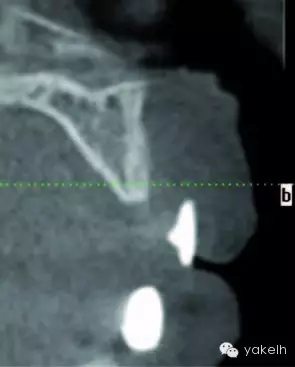

¤¤全景片以及根尖片可用于評估骨缺損、周圍的牙列以及局部解剖形態(tài)。計算機(jī)斷層攝影(CT)對骨缺損的三維觀察十分有用,也能用于評估口內(nèi)供骨區(qū)的情況??山Y(jié)合使用種植設(shè)計軟件與CT掃描,更加精確地評估患者所需重建的骨量。使用計算機(jī)掃描制備頜骨的立體光刻模型,以制訂進(jìn)一步計劃。臨床醫(yī)生通過對架研究模型及診斷蠟型的研究分析,來把握牙槽嵴形態(tài)與預(yù)期修復(fù)結(jié)果的關(guān)系[7]。它們也可用于CT掃描中X線模板的制備[8]。該模板阻射影的輪廓,提示了修復(fù)體在殘余牙槽嵴斷層掃描的位置(圖13.1,圖13.2)。這有助于決定所需移植骨的大小以及取骨的部位。在骨移植手術(shù)中,設(shè)計預(yù)期修復(fù)體位置的模板,對于移植物植入位置的確定以及完成骨移植的要求也是很有用的。

圖13.1 上頜骨外傷的患者,戴入含鋇的X線檢查模板。

圖13.2 X線模板的CT掃描,模板輪廓提示了預(yù)期修復(fù)體位置與殘余牙槽嵴的位置關(guān)系。